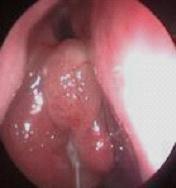

鼻炎长期得不到有效治疗导致鼻息肉以及鼻腔囊肿

经常鼻塞、流脓鼻涕、头痛多为鼻窦炎、鼻息肉等。 除了流鼻涕外,长期伴有头疼症状。是早晨疼还是夜间疼?怎么减轻症状?在线咨询为你解答。